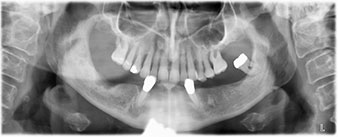

Пациентката е 64-годишна жена с частично обеззъбяване на зъби 38, 33 и 43 и частична долночелюстна протеза (Фиг. 1 и 2).

Направи се скенер с триизмерна компютърна томография (CBCT, Planmeca), за да се подпомогне планирането и да се намалят рисковете. Той показа, че качеството и количеството на наличната кост са достатъчни за операцията и имедиатното възстановяване, използвайки Fast & Fixed метод. Следвайки протокола за тази концепция, имплантите са поставени на 35, 32, 42 и 45 позиция. Ангулирането на дисталните импланти до 45° промени профила в задната зона и осигури по-голяма поддръжка в многоъгълната зона (Фиг. 3).